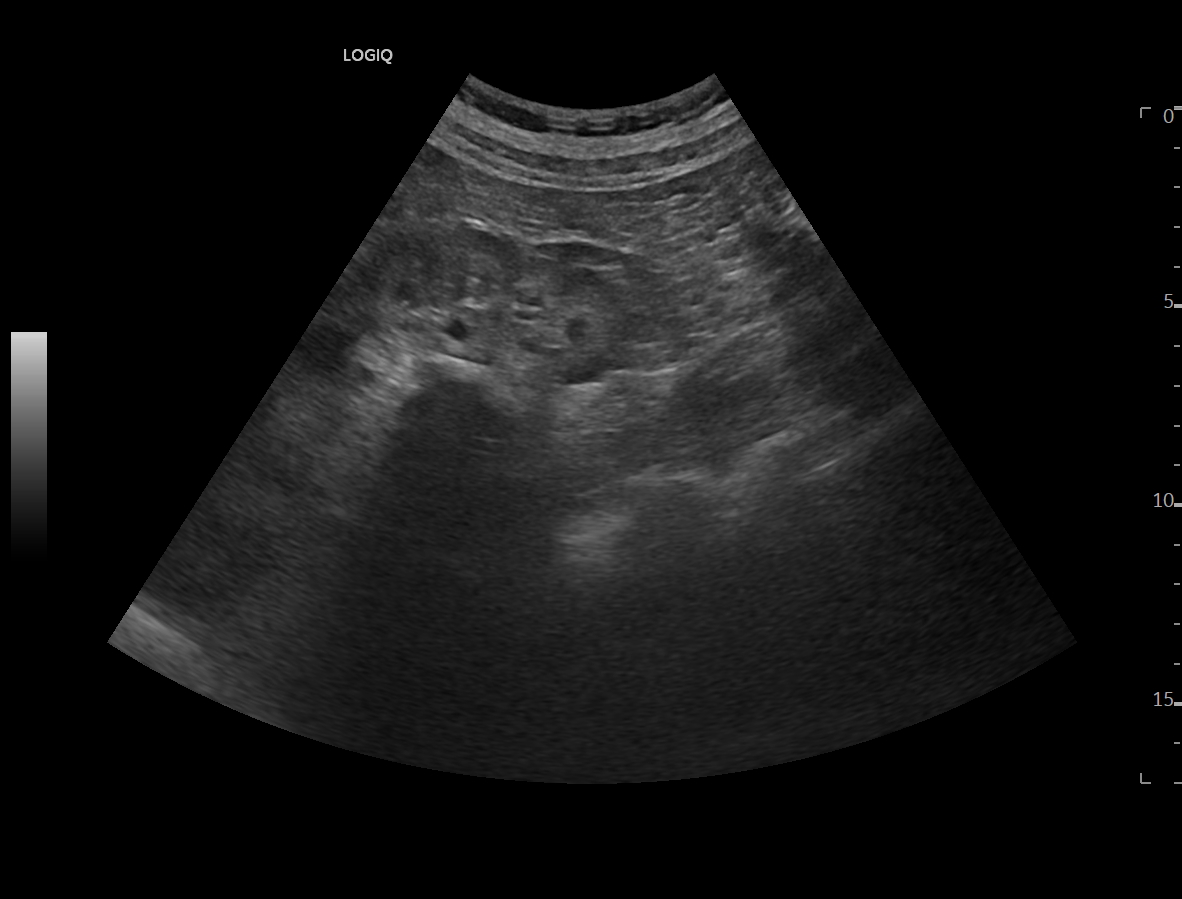

Ya en urgencias hospitalarias, se realiza ecografía clínica donde se aprecia ureterohidronefrosis derecha grado IV con pérdida completa de ecoestructura renal por el incremento del volumen que presenta, no presentando las mismas alteraciones en el lado izquierdo, pudiendo esto indicar una obstrucción completa no resuelta.

La ecografía clínica reglada informa de dilatación de pelvis renal de hasta 5,7 cm con aumento de tamaño renal hasta 13 cm, apreciando litiasis obstructiva de 12 mm en uréter distal a unos 5 cm del meato ureteral derecho.